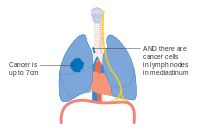

Lung cancer staging is an assessment of the degree of spread of the cancer from its original source.[71] It is one of the factors affecting the prognosis and potential treatment of lung cancer.[6][71]

The evaluation of non-small-cell lung carcinoma (NSCLC) staging uses the TNM classification. This is based on the size of the primary tumor, lymph node involvement, and distant metastasis.[6]

Using the TNM descriptors, a group is assigned, ranging from occult cancer, through stages 0, IA (one-A), IB, IIA, IIB, IIIA, IIIB and IV (four). This stage group assists with the choice of treatment and estimation of prognosis.[73]

- Diagrams of main features of staging

Stage IIIA lung cancer

Stage IIIA lung cancer, if there is one feature from the list on each side